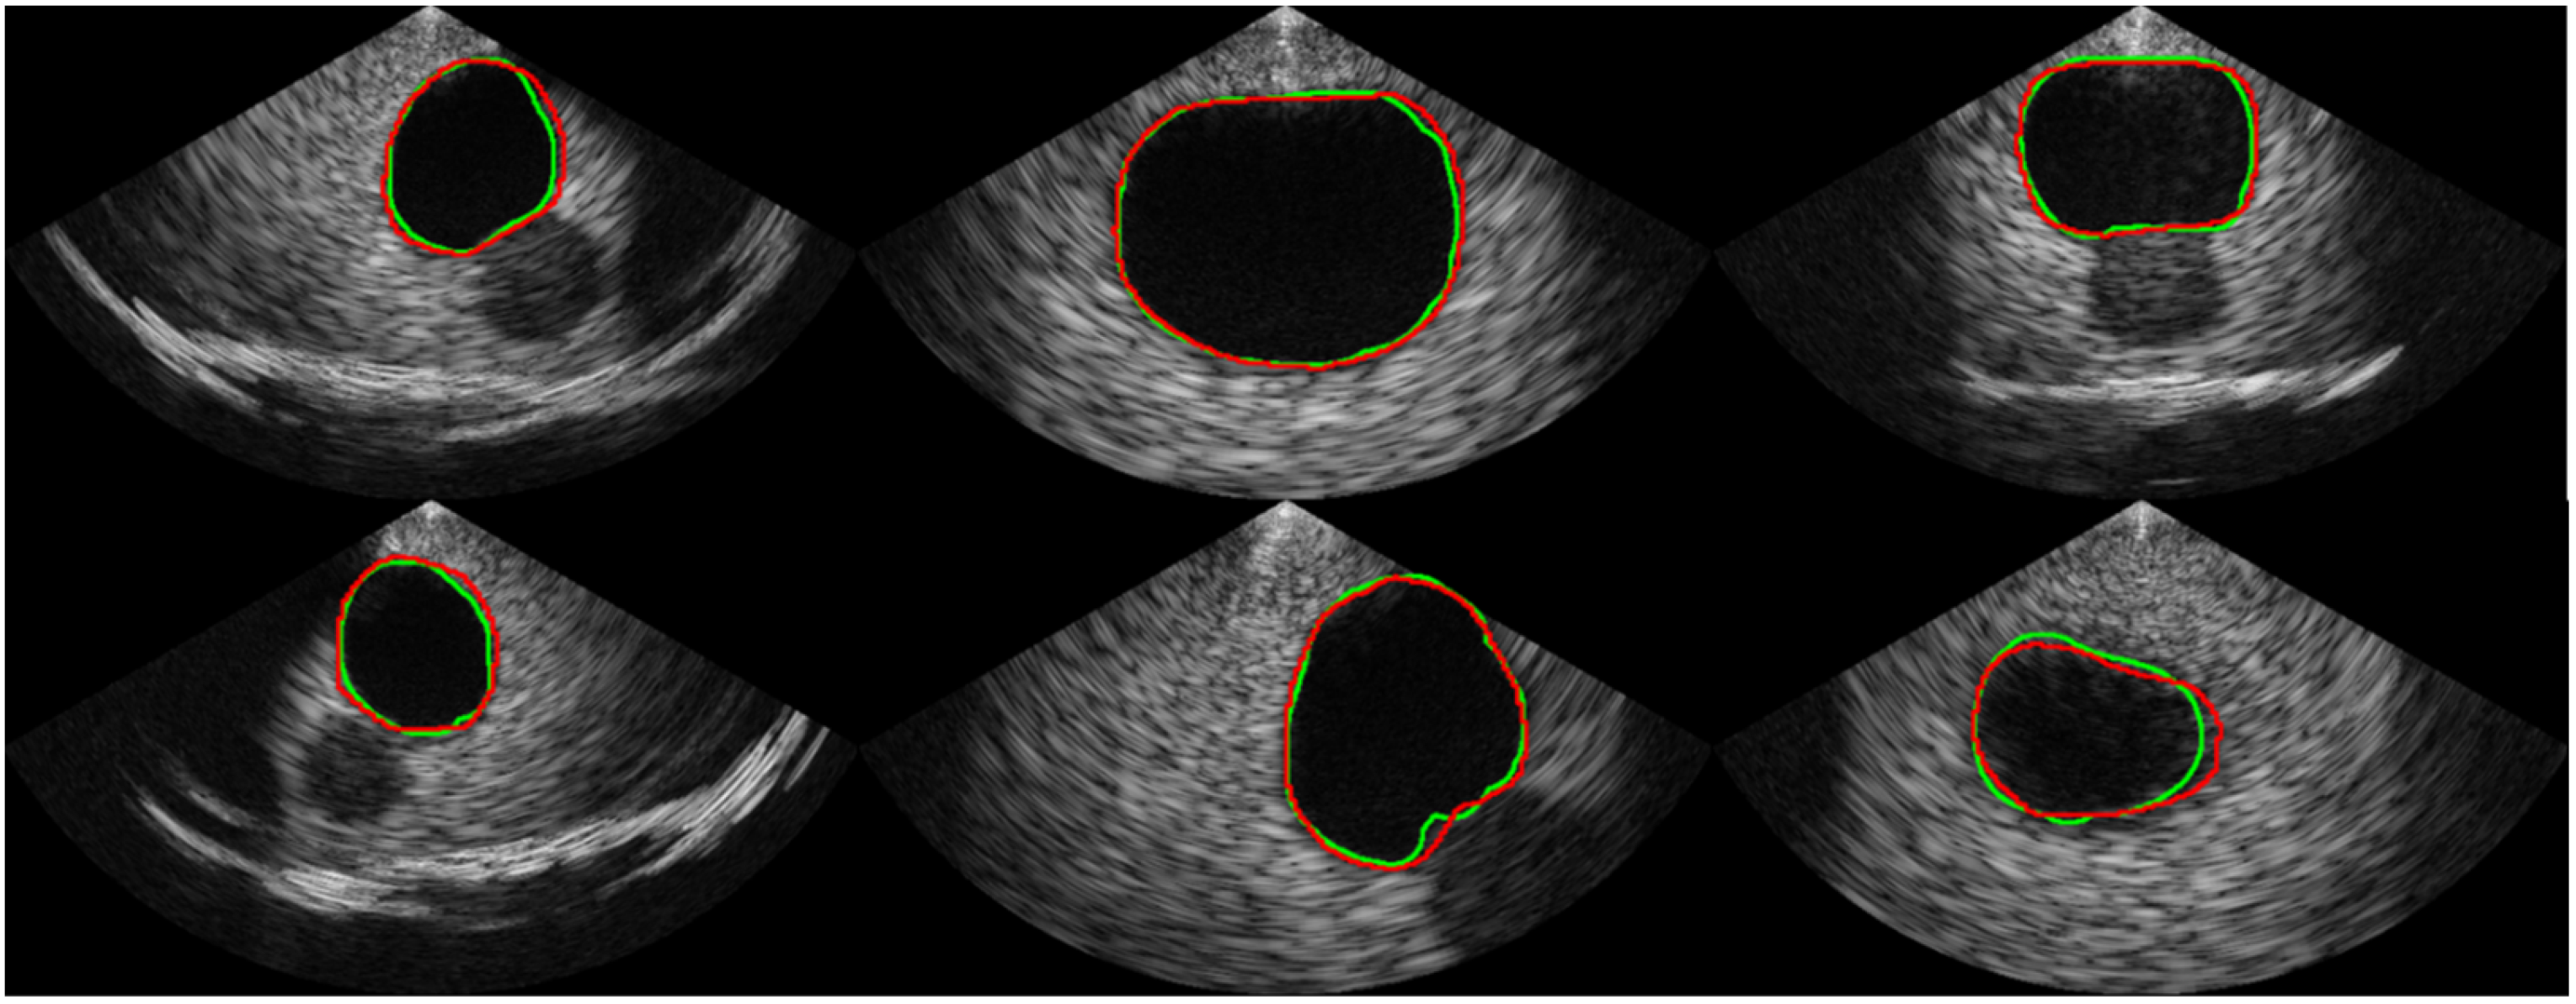

Figure 6.

Examples of the segmentation result. The ground truth is represented by the green line, while the prediction from our proposed network is represented by the red line.

Table 1 shows the comparison of the proposed segmentation path with conventional CNN-based segmentation networks. U-Net, which is commonly used as a baseline for medical image segmentation, achieved an average Dice coefficient of 0.913 with a standard deviation of 0.124. The implemented U-Net had 8.56 million parameters and a throughput of 1.33 frames per second (FPS) in the SoC environment. In comparison, the Attention U-Net achieved a much higher Dice coefficient of 0.944 on average with a standard deviation of 0.075 but had a slower throughput than the U-Net, despite having fewer parameters. The recently introduced BiSe-Netv2 showed even higher Dice coefficients than both U-Net and Attention U-Net (i.e., an average of 0.958 and a standard deviation of 0.034) with even fewer parameters. However, BiSeNetv2 was slower than U-Net, running at less than 1 FPS. In contrast, the proposed method had significantly fewer parameters (i.e., 0.97 million) and could be executed at a much faster rate of approximately 8 FPS, which was 5.96x , 52.87x, and 13.44x faster than the U-Net, Attention U-Net, and BiSeNetv2, respectively. Although the proposed method had a slightly lower Dice coefficient than BiSeNetv2 (i.e., 0.954 ± 0.045 vs. 0.958 ± 0.034, respectively), the segmentation results from the proposed network are promising, as shown in Figure 6. The validation accuracy of the classification path was over 0.99, indicating high accuracy in the classification results, as shown in the confusion matrix in Figure 7.